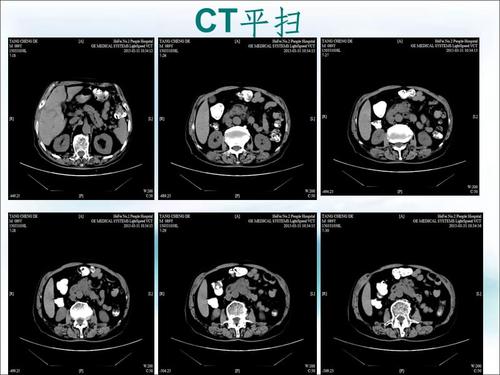

癌症CT图片,癌症ct片子图片

入院时ct,可见巨大肿瘤

胰腺癌ct表现

很多年前的片子了 我父亲的 想知道到底什么样的癌症 上几张ct图吧

小肠良恶性肿瘤的ct诊断